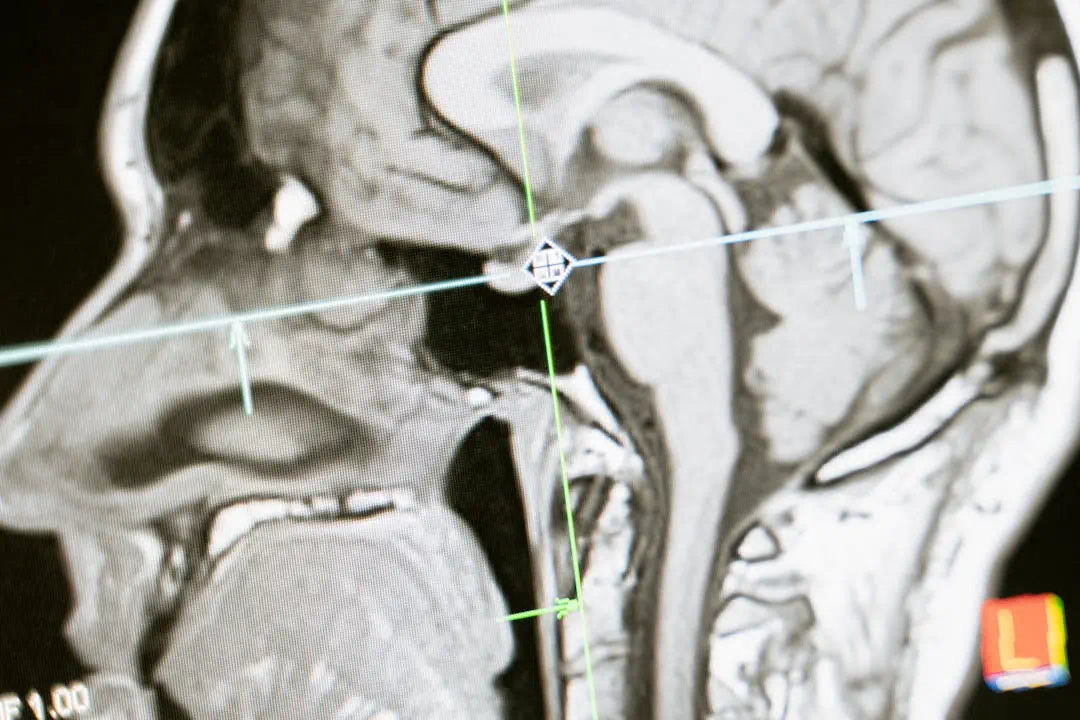

뇌경색 수술하고 있는 의사들뇌경색 수술을 하고 있는 의사의 모습뇌경색 MRI를 확인하고 있는 의사들

뇌경색 초기증상 놓치면 위험합니다

뇌경색 관련사진으로 두통의 모습을 표현4뇌경색 관련사진으로 두통의 모습을 표현5뇌 MRI 사진의 모습